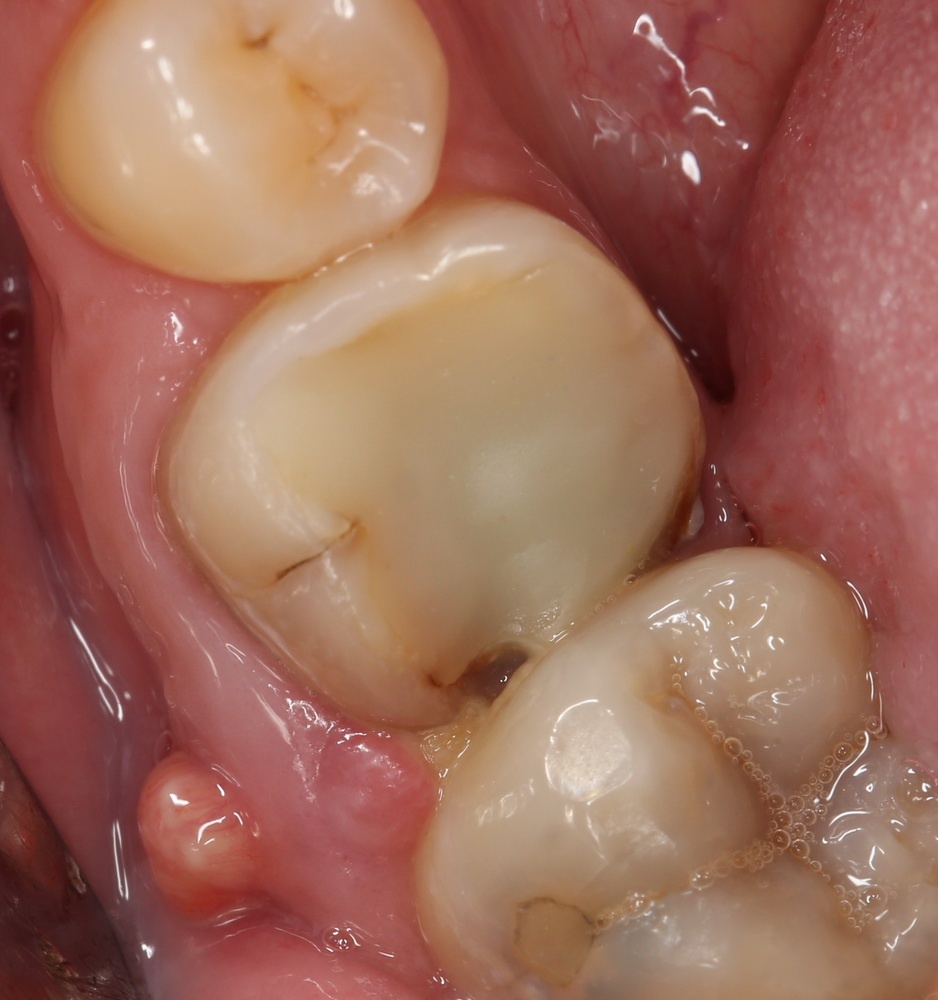

Через день-два лунка удаленного зуба выглядит следующим образом:

Постепенно кровяной сгусток из темно-бордового превращается в желтовато-белый. Связано это с тем, что красная его часть (эритроциты и гемоглобин) вымываются ротовой жидкостью, остается только фибриновый каркас. Многие пациенты путают его с гноем, пытаются вычистить. Не нужно этого делать.